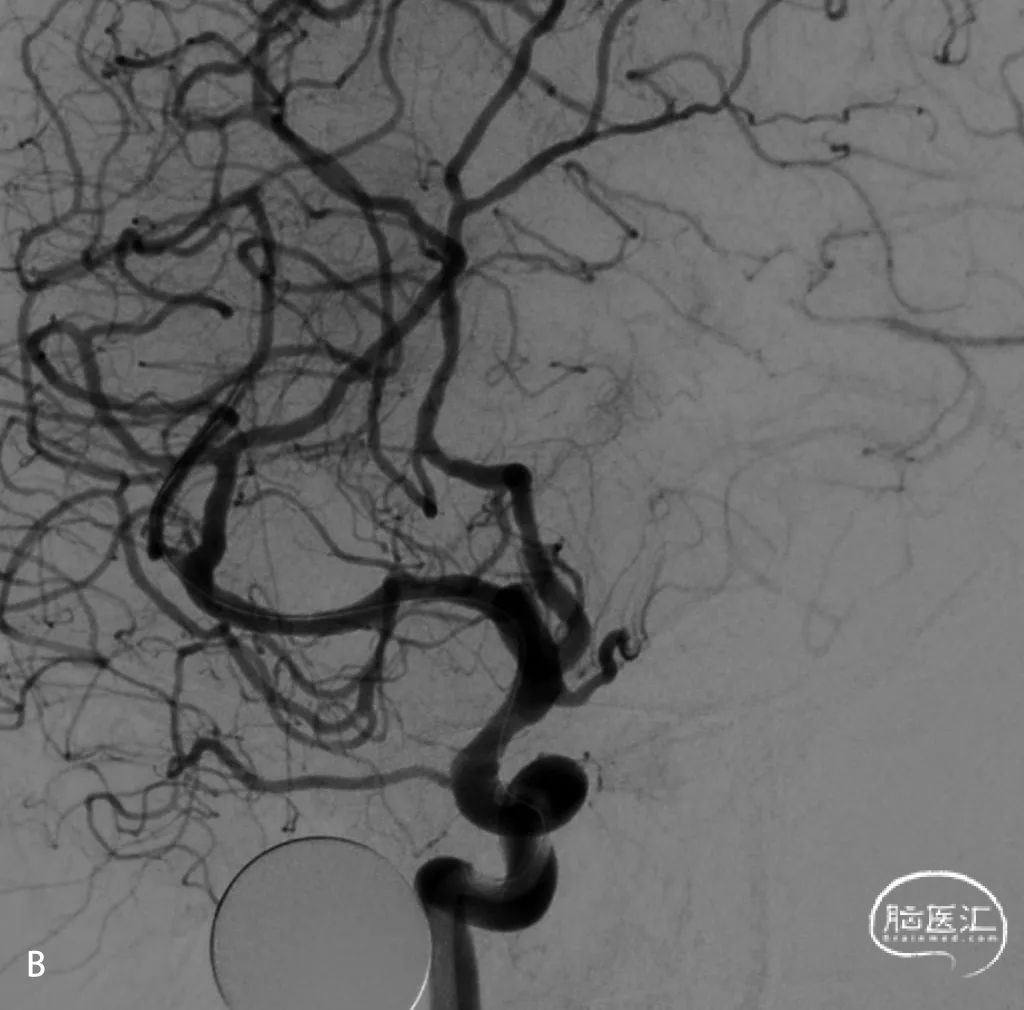

常规消毒铺巾,局部麻醉后,右侧远端桡动脉置入6F泰尔茂动脉鞘,全身肝素化;桡动脉造影提示桡动脉管径较大(图1.A);主动脉弓造影提示I型弓(图1.B)

图2.A为6F-Tethys®中间导引导管通过裸管技术进入主动脉弓;B为SIM2在主动脉弓成袢,图2.C为6F-Tethys®中间导引导管超选入右侧颈内动脉。